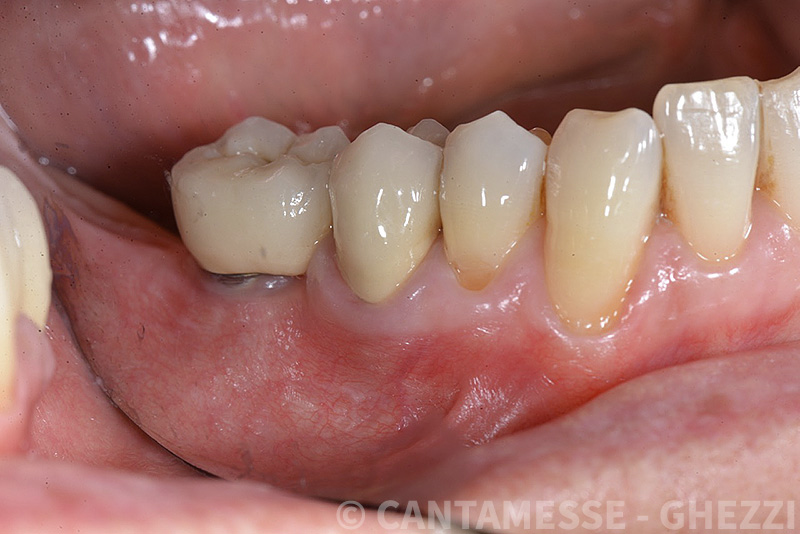

Vengono utilizzati 2 tipi di provvisori: il primo, cementato ai denti vicini, viene utilizzato dal momento dell’estrazione del dente fino ad impianto osteointegrato (circa 6 mesi); il secondo, avvitato direttamente all’impianto, ha una funzione di prova estetica ma soprattutto di guida per la maturazione dei tessuti gengivali peri-implantari portandoli verso la maturazione completa prima di posizionare la corona finale in disilicato di litio.